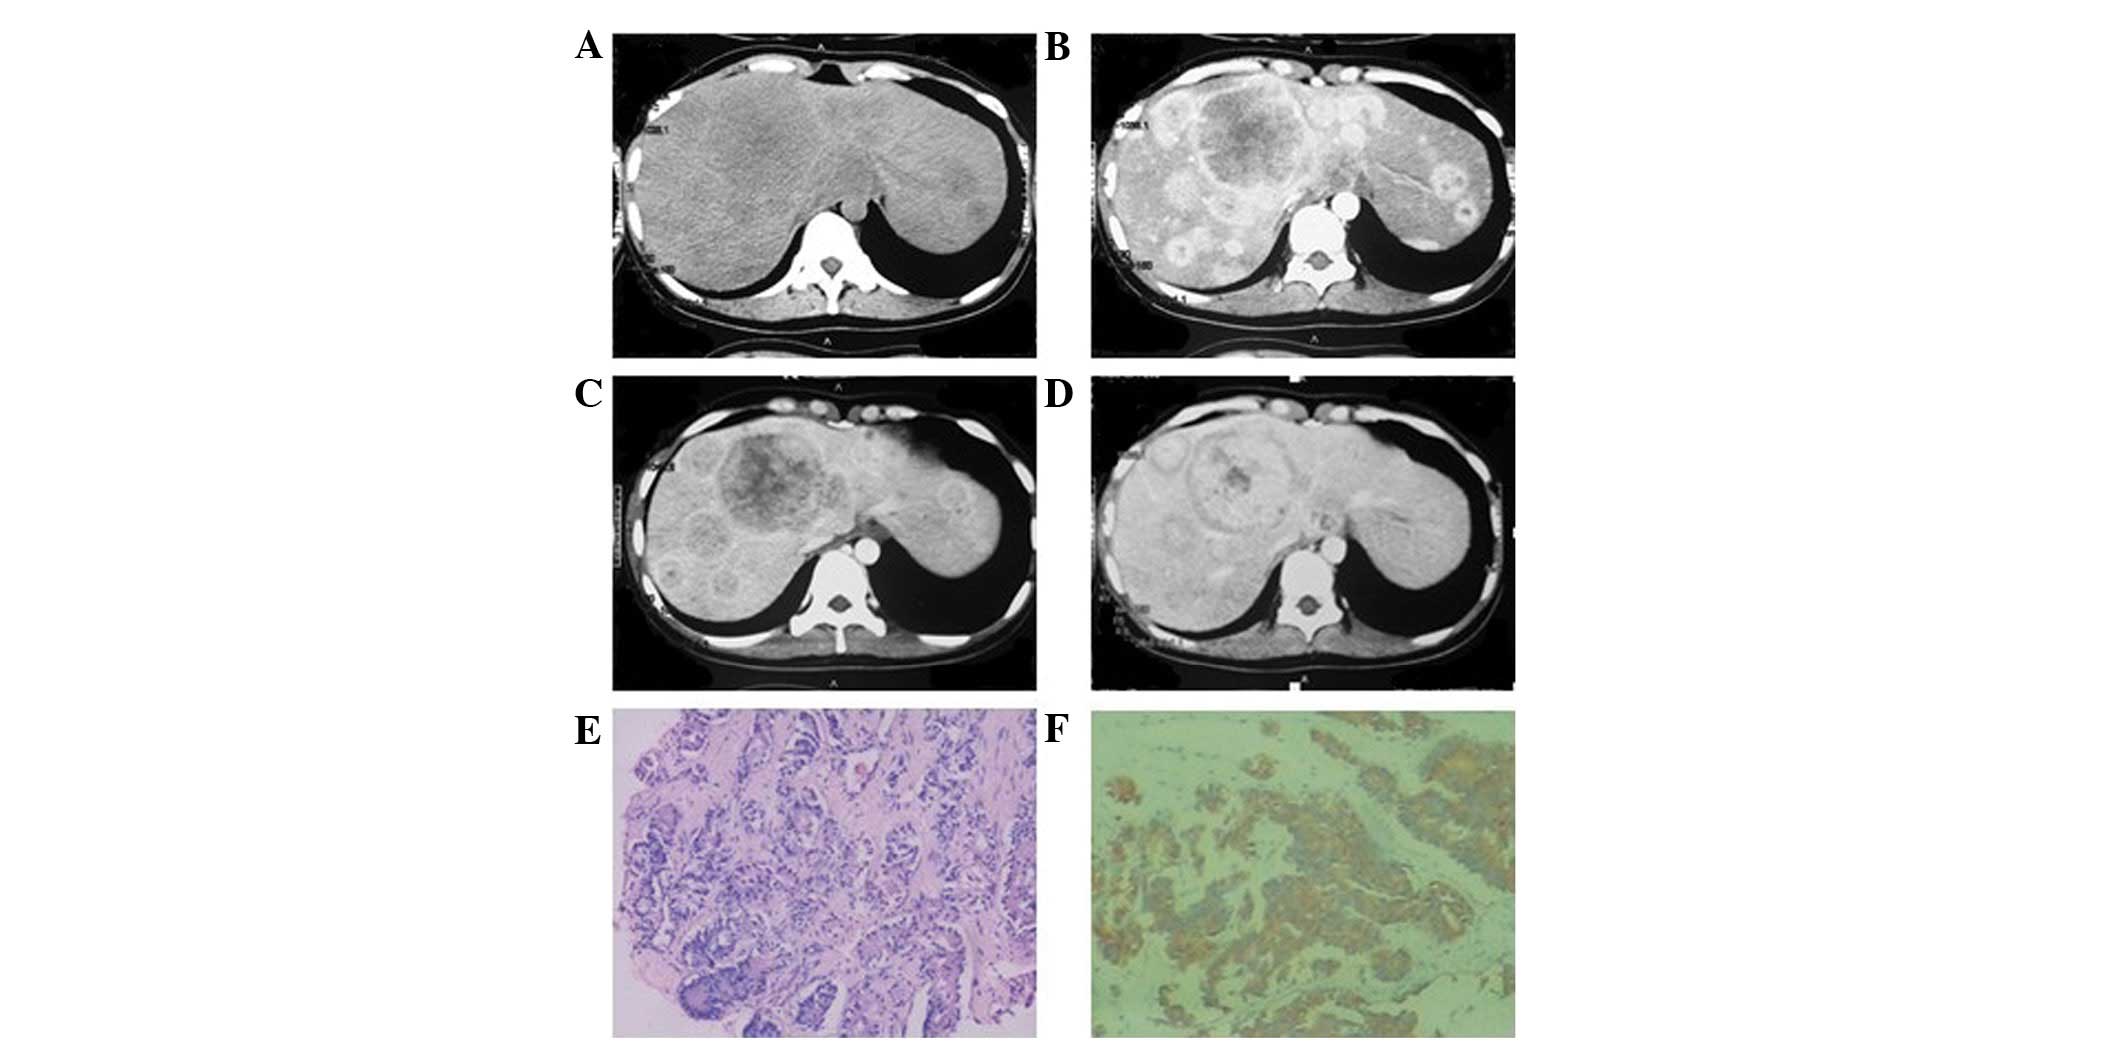

In the eight patients exhibiting multiple intrahepatic lumps, the foci were of various sizes. In four patients, the diameters of the largest foci were >7 cm whilst in the remaining four, the diameters were <2 cm. Plain CT scan showed low-density lesions. The four cases with larger masses had a lower density liquefied necrotic area (Figs. 2A, 3A and 4A) while the four cases with smaller foci had a relatively uniform density (Fig. 5A). The boundaries of the foci were unclear in six patients (Figs. 3 and 5), while they were clear in the other two cases (Fig. 2). All foci showed uneven enhancement in the arterial phase, six of which exhibited annular enhancement (Figs. 2B–4B). In six patients, the degree of enhancement was found to decline in the portal venous phase (Figs. 2C, 3C and 4C) and the delayed phase (Figs. 2D, 3D and 4D). In two patients, the enhanced area was enlarged in the portal venous phase (Fig. 5C) and the enhancement extended over a long period of time. The degree of enhancement in the delayed phase (Fig. 5D) declined in all cases, and the density of the foci was generally uniform. In one patient (Fig. 6), the foci were not observed in plain scanning but were clearly observed in the arterial phase and absent in the portal venous and delayed phases.

Figure 2

Well-differentiated neuroendocrine carcinoma in a 34-year-old female. (A) Precontrast computed tomography showed multiple lumps of various sizes in the right and left hepatic lobes with a maximum cross-section size of 6×5 cm, clear boundaries and uneven density. A liquefied necrotic area in the center of the largest focus was observed. (B) In enhancement scanning, an annular enhancement was observed in the arterial phase. (C and D) A decline in the enhancement was observed in the portal venous and delayed phases, respectively. (E–J) Magnetic resonance imaging showed multiple long T1 and T2 signal foci in the liver, which were nodular and lumpy which were markedly enhanced. (K and L) Hematoxylin-eosin staining (magnification, ×100 and 200, respectively) revealed morphological diversity of the tumor cells and vessel-like arrangement in parts, with similar morphological features and limited interstitial substance.

Carcinoid in a 24-year-old female. (A) Precontrast computed tomography showed multiple lumps of various sizes in the right and left hepatic lobes with obscure boundaries, uniform density and a maximum diameter of 7.5 cm. (B) In enhancement scanning, obvious enhancement was observed in the arterial phase and an annular enhancement was shown in the largest mass. (C and D) A decline in enhancement was observed in the portal venous and delayed phases, respectively. (E and F) Hematoxylin-eosin staining (magnification, ×100) and immunohistochemical staining, respectively. The tumor cells showed morphological diversity and vessel-like arrangement in parts, with similar morphological features and limited interstitial substance.